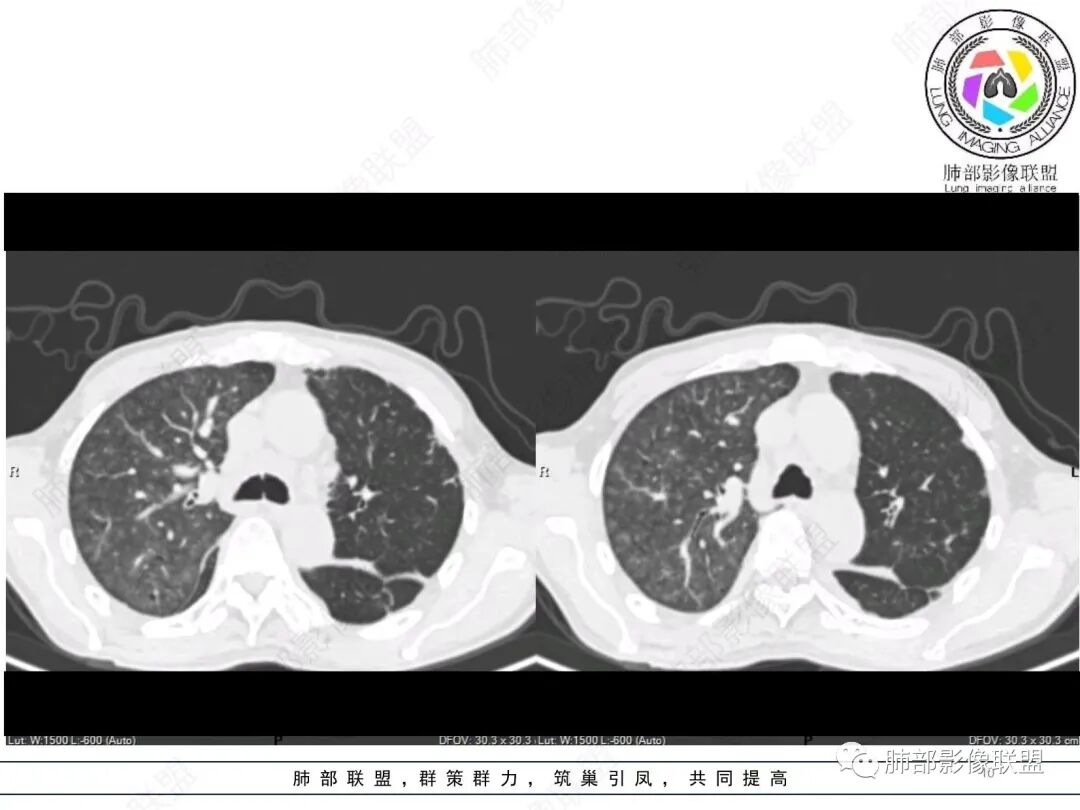

双肺叶透亮度呈磨砂状,并弥漫性以肺腺泡为单位GGO结节,边缘模糊,肺动脉高压表现,双肺下叶肺动脉分支明显增粗>邻近支气管径,小叶间隔增厚,叶间积液和少量胸腔积液,方向1.PVOD病并肺泡出血,2.心衰表现!

老年男性,胸闷、浮肿10天,左肺尖可见肺大泡影,两肺散在纤维索条影,右肺见弥漫性腺泡结节,以右肺上叶为著,右肺下叶局部小叶间隔增厚,双侧胸腔、右侧叶间裂及心包积液,结合实验室及影像检查,符合心衰及肺水肿表现,右肺部病变符合PVOD表现。

双肺透过度不均匀,右肺减低,可见腺泡结节影,中央间质、周围间质增厚,少量积液。肾衰病史首先考虑肾性肺水肿。

肺水肿有的,可能心源性的,但导致的原因仍需进一步排查,虽有肾功能但不像肾源性,虽有肺动脉高压,但不考虑PVOD(年龄,性别,肺动脉高压可能由于瓣膜,心衰继发)。二聚体高,右肺胸膜下反晕病灶,肺梗要排除。另外就是右单肺腺泡结节以及带晕的实性结节。这个怎么解释。虽有误吸危险因素,但临床没有发热,血象不高。

这些小叶间隔增厚明显区域反而GGO少

支持间质性肺水肿改变,PVOD我不太支持。

按理是肺静脉的增粗、小叶间隔增厚,导致局部血液回流受阻,逆向肺动脉高压,就是GGO应该在小叶间隔增厚区为主,而且肺动脉主干的双侧不受影响。这个肺部改变符合肺动脉高压所致。也就是毛细血管前的更符合

2、双侧胸水,小叶间隔光滑增厚——支持间质性肺水肿,提示心功能不全

3、右肺改变符合肺动脉高压导致

4、肺动脉改变:左肺动脉起始部突然狭窄(右肺动脉代偿增大——继发肺内改变)

2.右肺广泛密度增高、腺泡结节样磨玻璃影,血管影明显扩张,小叶间隔增厚。

3.右肺下叶纤维钙化灶。

4.左肺相对广泛低密度、血管纤细(显著)。